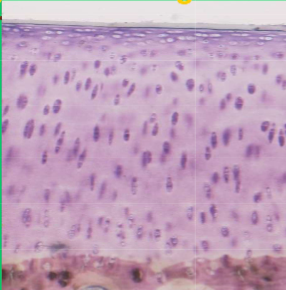

What tissue is primarily shown here

Hyaline cartilage

What are the components of Hyaline cartilage

A.

B.

C.

A. Collagen type 2

B. PSGAG

C. Hyaluronic acid

What cells make articular surface

Chondrocytes make all components of the Hyaline cartilage